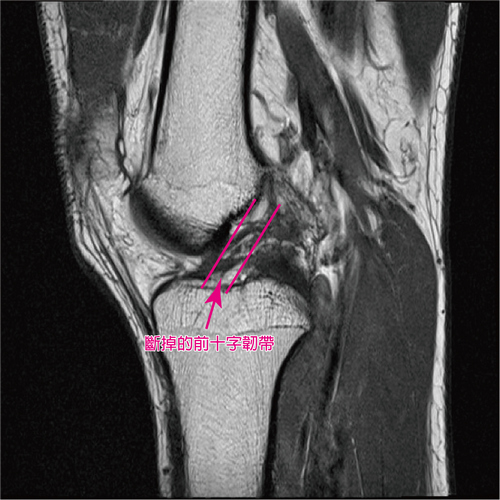

病人手術前前十字韌帶與術後三個月的磁振造影檢查(MRI) 影像,明顯看出復原情形。

劉冠麟主任指出,膝關節前十字韌帶損傷有一個特點,一般骨折會因血管破裂導致血液淤積,壓迫周圍組織造成發炎,慢慢的體內生長物質就會包覆住受傷部位,出血並產生血腫,但前十字韌帶損傷,膝關節內關節腔的血會滲到周圍,沒有血腫也不會癒合,所以一定要手術才能治好。